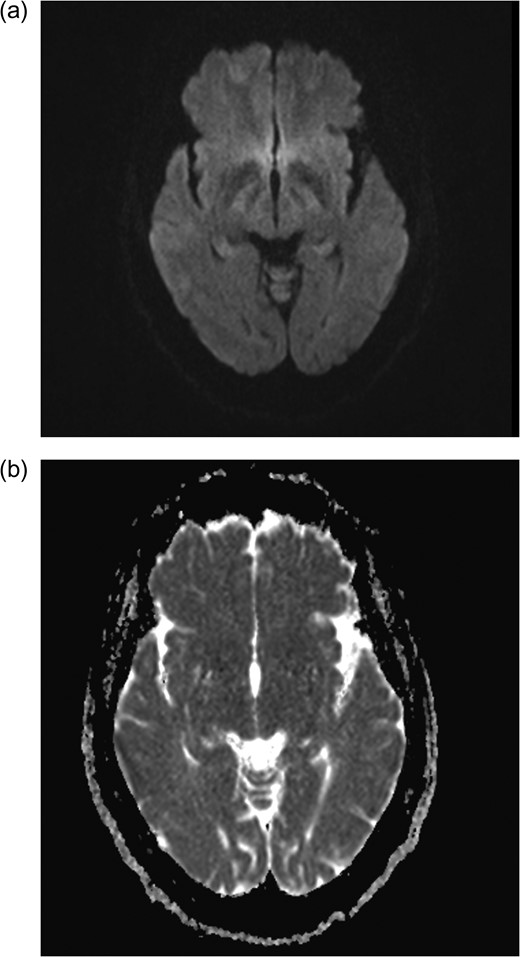

MRI brain axial T2 FLAIR sequence (October 2016) depicting resolution of right medial temporal lobe high signal but prominence of periventricular hyperintensity in periventricular white matter (arrows).

December 2015, she had a normal electroencephalogram (EEG). Subsequent MRI done January and March 2016 showed T2 Weighted Imaging Fluid Attenuated Inversion Recovery (T2WI/FLAIR) changes in the right medial temporal lobe (Fig. 2). Right hippocampal signal change was suspicious of low-grade glioma with a differential diagnosis of post viral limbic encephalitis. There was no enhancement with intravenous gadolinium administration and no other suggestion of a focal malignant disease. She remained clinically well and repeat MRI done October 2016 showed areas of signal abnormalities focused around the posterior horns of the lateral ventricles and but no sign of right temporal lobe low-grade glioma or encephalitis (Fig. 3). All of these signal changes resolved completely with repeated MRI and she had no further seizures.